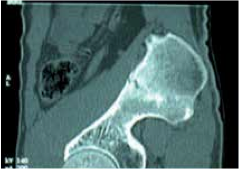

TDM à deux mois.